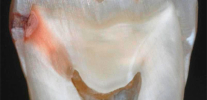

La foto sotto mostra la carie nascosta nel dente estratto (situato sulla superficie di contatto, cioè nel punto di contatto con il dente adiacente). L'area interessata ha raggiunto la camera pulpare: